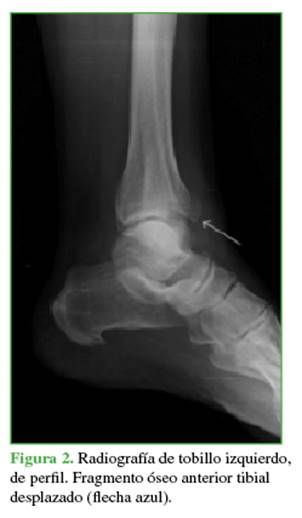

Paciente de 62 años, ama de casa, previamente independiente para sus actividades de autocuidado y funciones del hogar, con diabetes mellitus tipo 2 no insulinodependiente, hipertensión arterial controlada y hallux valgus bilateral asintomático. Acudió al Servicio de Urgencias de nuestra institución luego de un trauma en inversión al bajar un escalón, tras lo cual refirió dolor, edema, limitación para la bipedestación y la marcha. Tenía dolor a la palpación del cuello del pie, movilización espontánea de los dedos y pulso pedio palpable simétrico, no se observaron deformidades ni heridas. Ingresó para la toma de radiografías anteroposterior y lateral del tobillo derecho, que revelaron una asimetría en la unión tibio-peronea y pérdida en la continuidad articular tibial (Figuras 1 y 2).